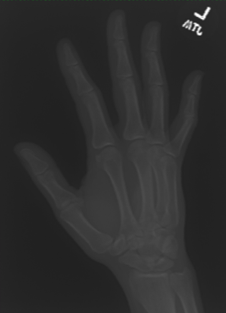

In this work, we focus on a subset of the MURA dataset [17] containing only hand images. In total, we have 5,543 images of 2,018 studies of 1,945 patients. Each study is labeled as negative or positive, where positive means that there was an anomaly diagnosed in this study. There are 521 positive studies, with a total of 1,484 images. Figure 1 shows some examples from the dataset. In summary, our contributions are as follows: